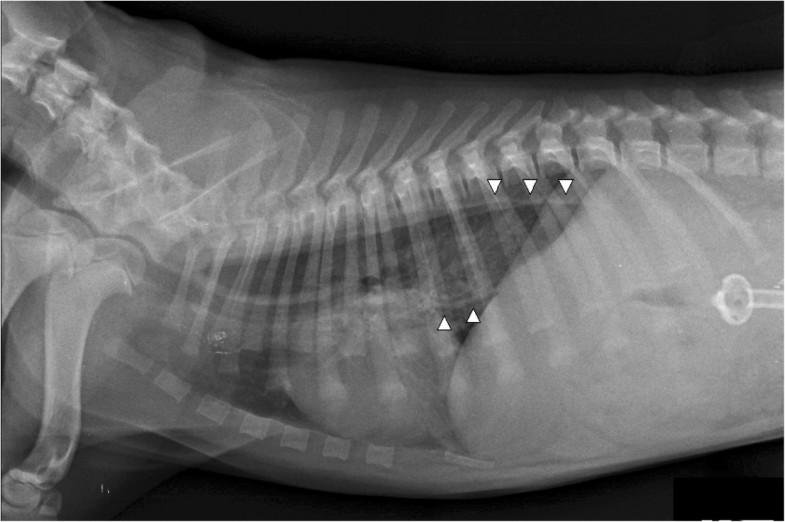

From www.semanticscholar.org

Figure 1 from Diagnostic imaging and endoscopic finding in dogs and Dog Endoscopy Risks flexible endoscopes are most commonly used for lower gastrointestinal endoscopy, as they allow evaluation of the entire length. endoscopy is now widely available for the investigation of gastrointestinal disease in dogs; pet endoscopy is a minimally invasive procedure for dogs and cats, aiding in the diagnosis of gastrointestinal issues, abnormal cells, tumours,. Franck jolivet and olivier dossin. Dog Endoscopy Risks.

Figure 1 from Diagnostic imaging and endoscopic finding in dogs and Dog Endoscopy Risks From vetovation, here’s what to know after a dog has an endoscope veterinary procedure. flexible endoscopes are most commonly used for lower gastrointestinal endoscopy, as they allow evaluation of the entire length. endoscopy is now widely available for the investigation of gastrointestinal disease in dogs; if your dog is experiencing stomach or esophageal issues, an endoscopy will. Dog Endoscopy Risks.